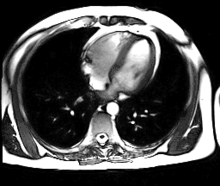

- استخدام الرنين المغناطيسي هو لغرض تشخيصي مثل تصوير الأوردة والشرايين، أو تصوير التغيرات العصبية في الدماغ، والرنين المغناطيسي يعتبر أفضل أنواع التصوير في توضيح الأنسجة وسوائل الجسم، وكذلك يستخدم لتخطيط الخطط العلاجية القائمة على العلاج الإشعاعي. قبل الفحص بالرنين المغناطيسي يجب مراجعة التاريخ المرضي والتأكد بشكل تام من عدم وجود جراحات سابقة أو حوادث أدت إلى تواجد معادن في الجسم مثل الشظايا، ويتم التأكد من ذلك عبر الفحص بالأشعة العامة الروتينية & مرور المريض من خلال كاشف معادن. يعطي المريض في الغالب صبغة خاصة تحقن في الجسم وذلك لزيادة التباين وتوضيح الأجزاء المتقاربة.

بدأت في بعض المستشفيات المتخصصة في العالم الغربي تطبيق طريقتين في نفس الوقت بغرض الحصول على تباين عالي وتوضيح كامل لحجم وشكل الورم السرطاني في العضو المريض، وطريقتي القياس تتم بواسطة التصوير بالرنين المعناطيسي وقياس آني بجهاز تصوير مقطعي بالإصدار البوزيتروني. تحتاج تلك الطريقة تواجد مركزا للبحث العلمي، بها سيكلوترون يقوم بتحضير النظير المشع وتنقيته ومعاملته (ربطه) بمادة حيوية مناسبة خلال وقت قصير، ثم يتم إرسال العبوة المجهزة إلى المستشفى الخاص حيث يكون المريض مستعدا على سرير العمليات لإجراء الحقن والقياس، وذلك لأن عمر إشعاع النظير المشع تكون قصيرة لمدة ساعات.